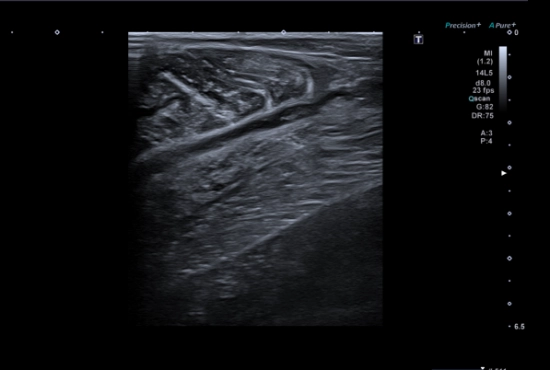

Quand des "tendinopathies achilléennes" cachent un piège poplité : l’importance de l’échographie dynamique et de l'examen clinique concomitant